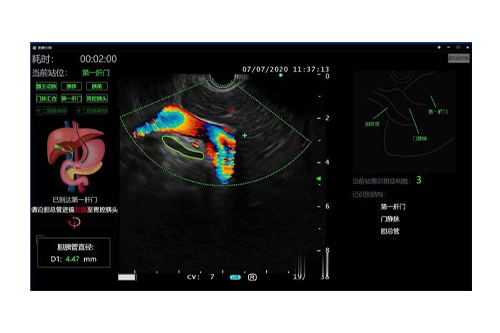

胆胰大师